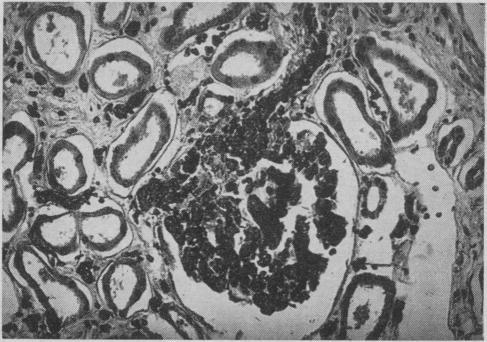

Some observations on glomerular vascular architecture.

Can Med Assoc J. 1957 Oct 1;77(7):679-86.